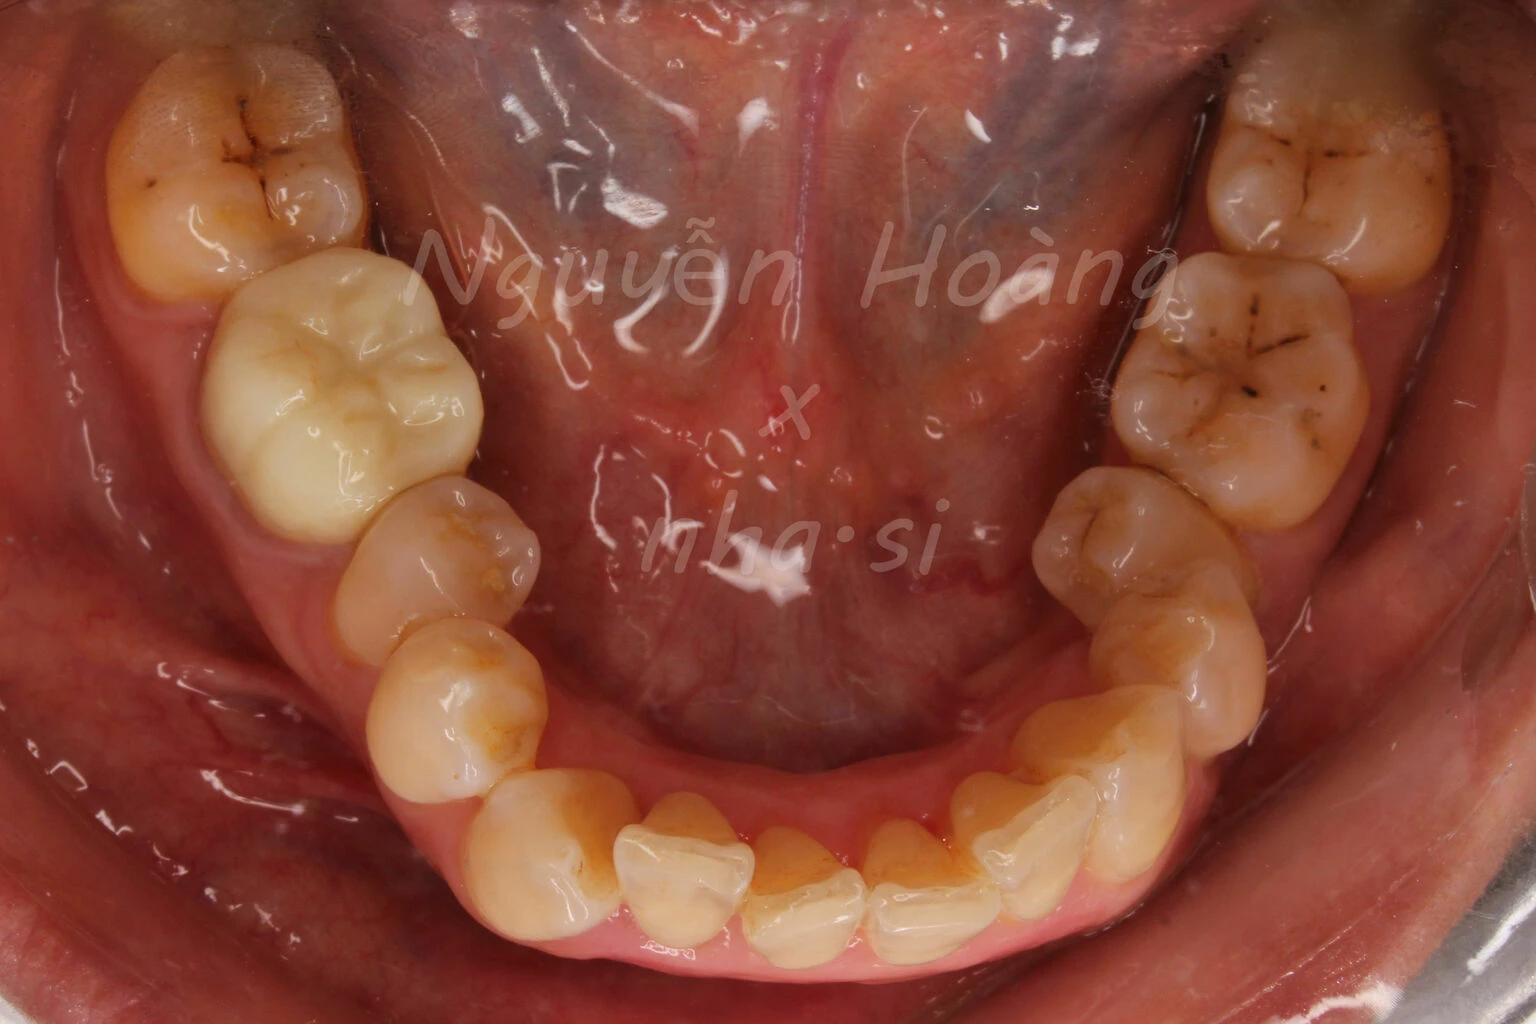

Hình 5: Sau gắn. Khách hàng hài lòng với bộ răng sứ thẩm mỹ.Nhìn từ phía ngoài, vị trí răng 5 được chụp sứ “làm đầy” hơn so với vị trí răng cũ.